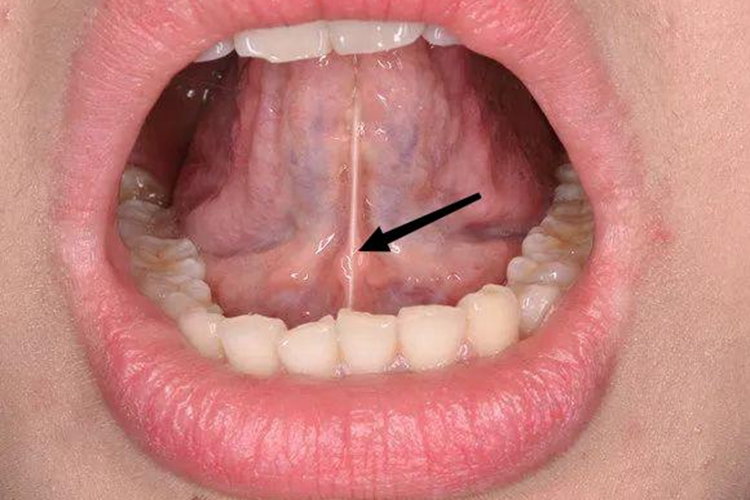

舌系带是舌下面黏膜在舌的正中线上形成的黏膜皱襞,看起来平滑而且薄,折返与口底黏膜相连,向下连于口腔底前部,在张口翘起舌头时可看到。

如果出生后舌系带没有退缩到舌根下,导致舌系带上份附着靠近舌尖,或其下份附于下颌舌侧的牙槽嵴上,称为舌系带过短。

此时患者表现为舌头不能正常自由地前伸,或者舌前伸时舌尖因被系带牵拉而出现凹陷,舌尖呈W形。部分孩子张口时舌尖不能上翘,不能舔到上齿龈或伸过上唇,年龄稍大后则影响正常发音,对咀嚼功能影响也较大。